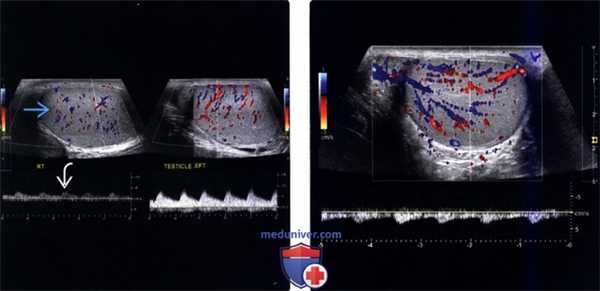

(Слева) Цветовое допплеровское картирование, сагиттальная плоскость, молодой мужчина с болью в правой половине мошонки: визуализируется асимметричный кровоток с уменьшением потока в правом яичке, что видно на цветовом потоке и спектральном анализе. Во время операции подтвержден частичный перекрут яичка на 180°.

(Справа) Цветовое допплеровское картирование, поперечный срез, правое яичко после деторсии: определяется реактивная гиперемия.